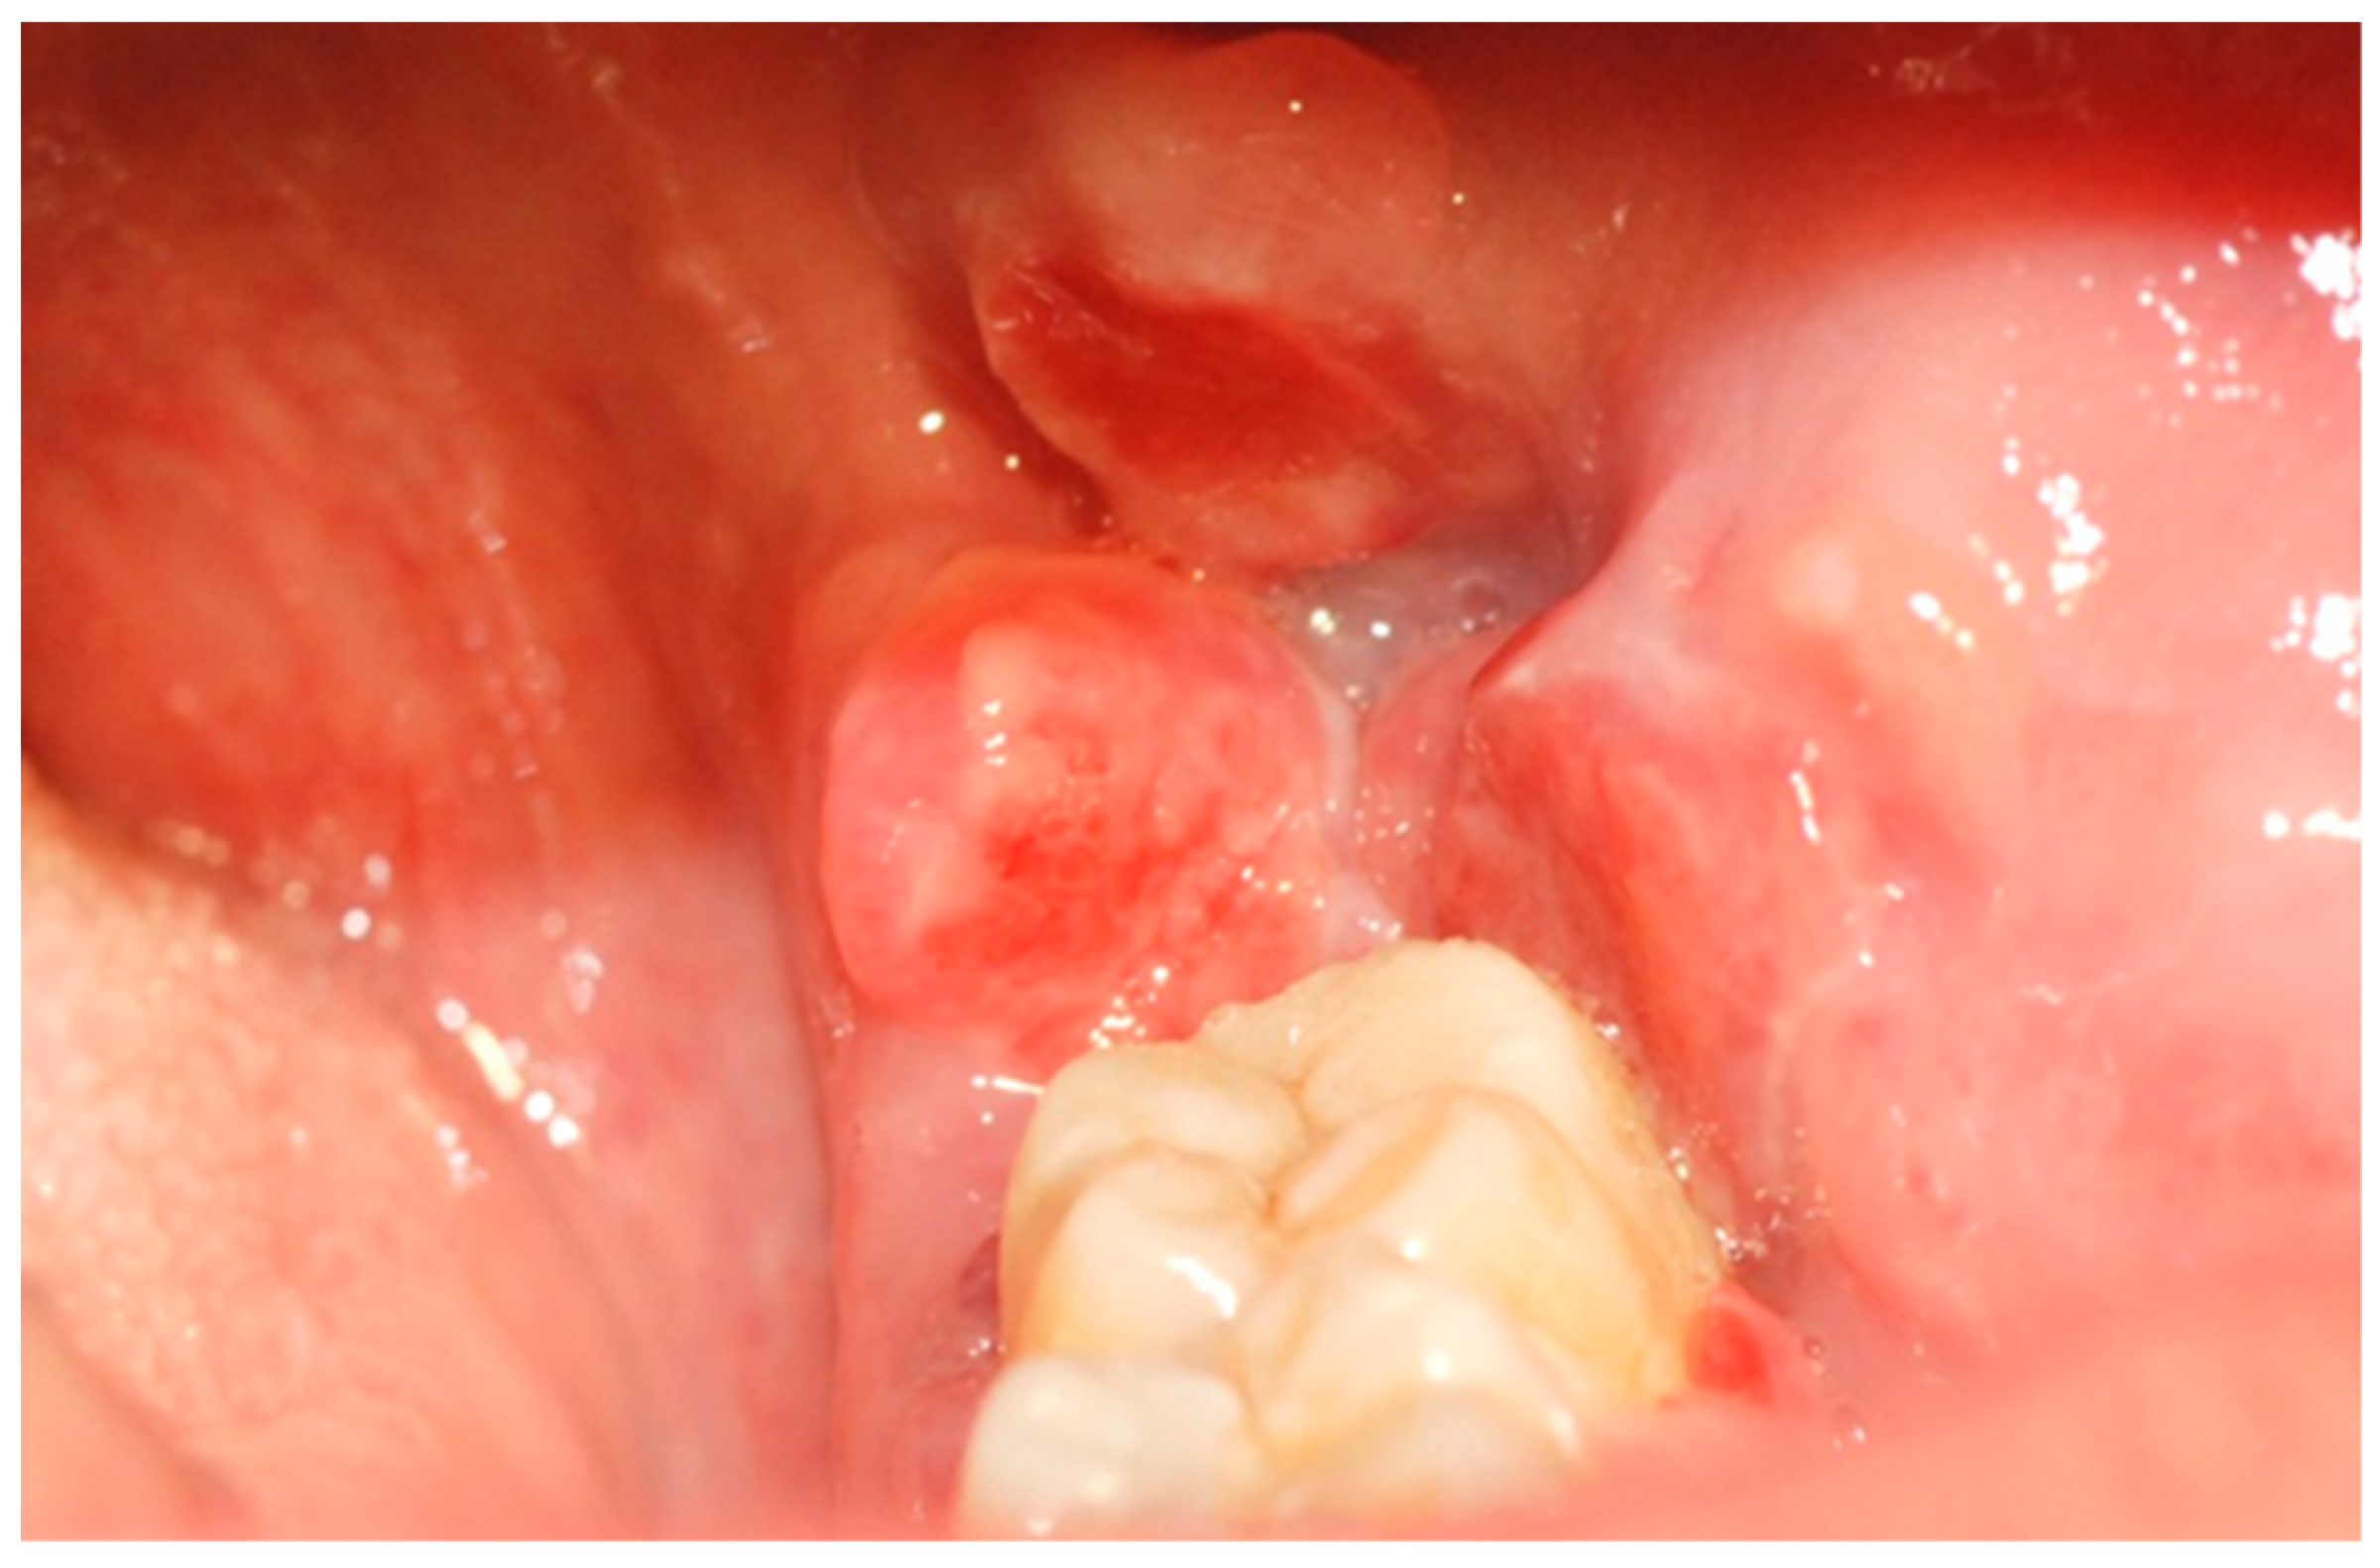

A 39-year-old Caucasian woman was referred to the Department of Oral and Maxillofacial Sciences of Polyclinic Umberto I, “Sapienza” University of Rome, for the presence of an exophytic and erythematous lesion located at the left retromolar trigonum (Figure 1), occurring since about 2 months, associated with a radiolucency evidenced by orthopanoramics (Figure 2).

Figure 1. Erythematous and exophytic lesion located at the left retromolar trigonum.